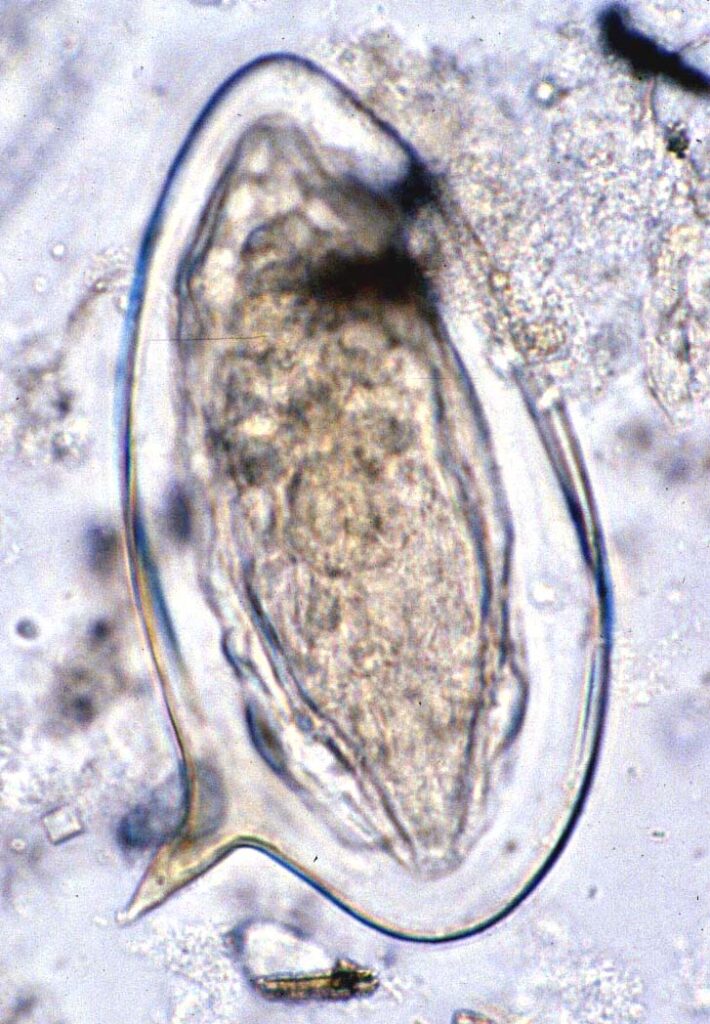

Uova Schistosoma mansoni